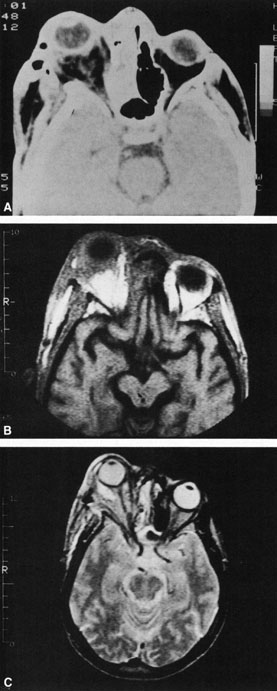

A subperiosteal abscess may rupture or invade the periorbit, resulting in an orbital abscess. This may or may not be contiguous with the subperiosteal collection on CT. There may be gas or air–fluid levels within the mass.51,56,58,59 An orbital abscess may present as an enhancing ringlike peripheral mass that can be either heterogeneous or homogeneous (Fig. 18).

Fig. 18. Orbital abscess. A. Computed tomography of an orbital abscess presenting as an enhancing intraconal mass on right side. B. T1-weighted image. C. T2-weighted image. Note area of high signal corresponding to abscess.

Magnetic resonance imaging (MRI) is purported to be more useful than CT in the diagnosis of preseptal cellulitis. It is less reliable at diagnosing the subtle signs of muscle enlargement and periscleritis and thus is not as useful in differentiating orbital cellulitis from other inflammatory orbital diseases.71 On MRI with gadolinium contrast, orbital cellulitis may show a smearing or linear streaking of the normal fat shadows on T2-weighted images. MRI is excellent for demonstrating localized fluid collections such as abscesses. It is not helpful in distinguishing a transudate from an exudate, because both appear liquid and are of low intensity on T1-weighted images and bright on T2-weighted images (Fig. 19).